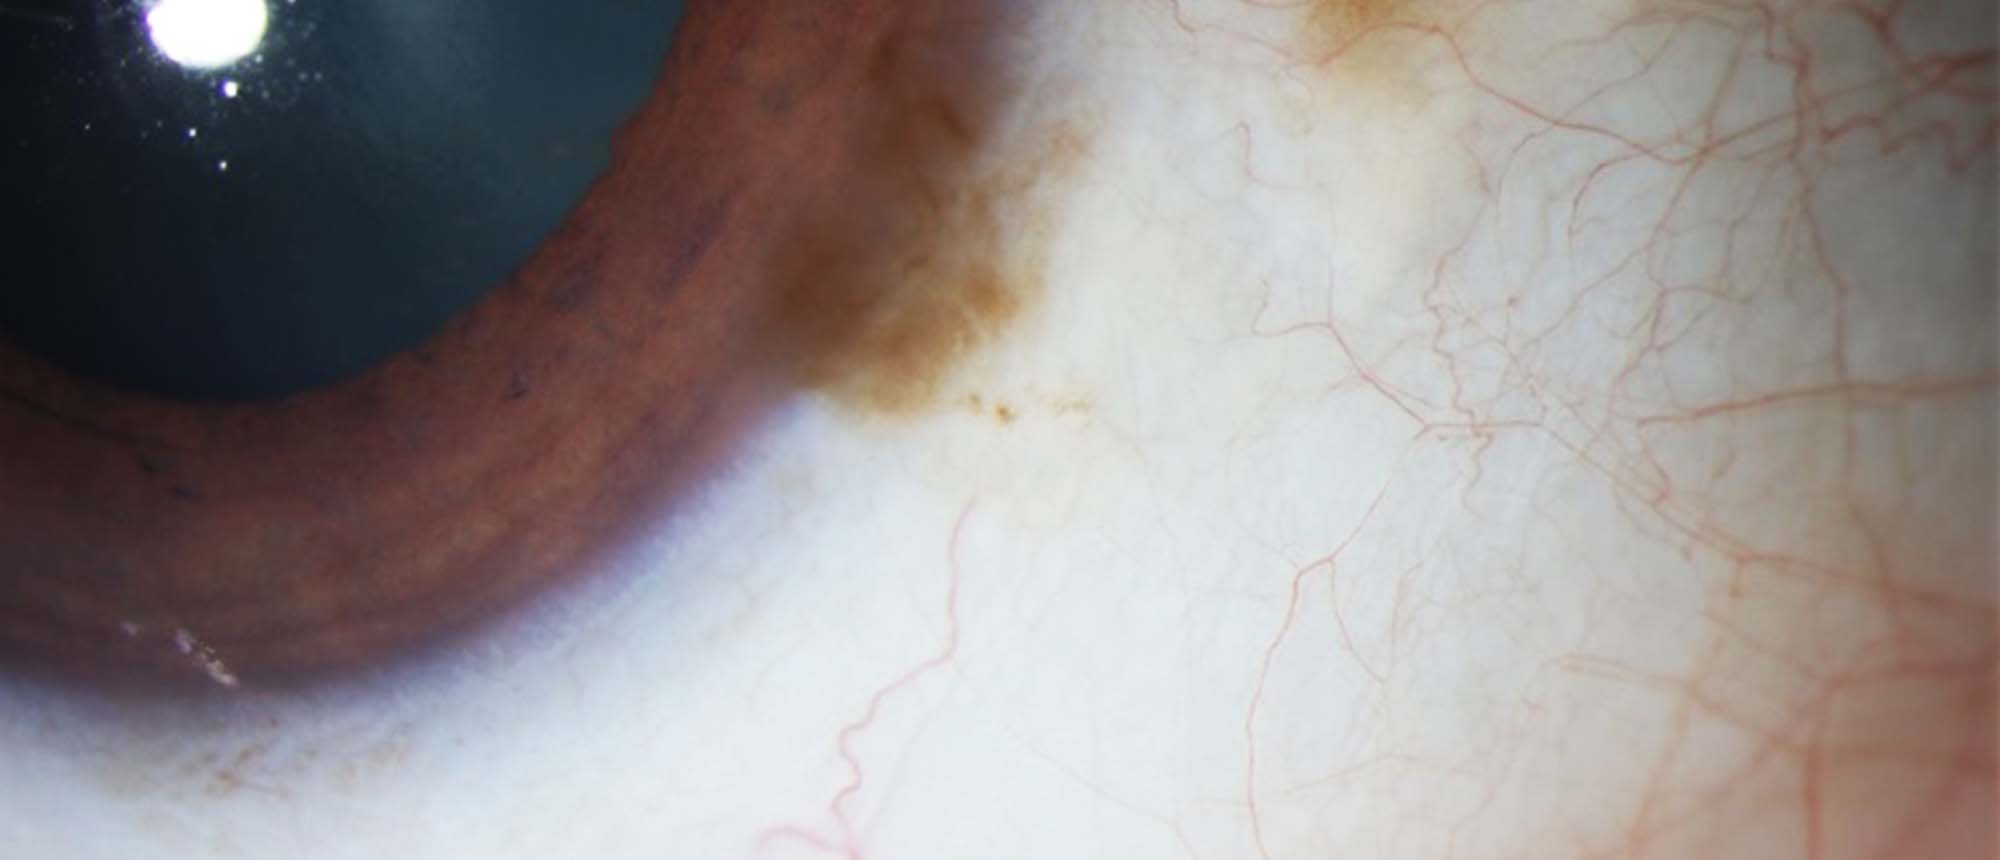

Smooth Muscle Hamartoma Our patient presented due to a one-year history of a slowly growing conjunctival lesion. A large, red, non-tender lesion of the right bulbar conjunctiva was identified on examination. It did not improve after several weeks of medical management with steroids. He had no previ…